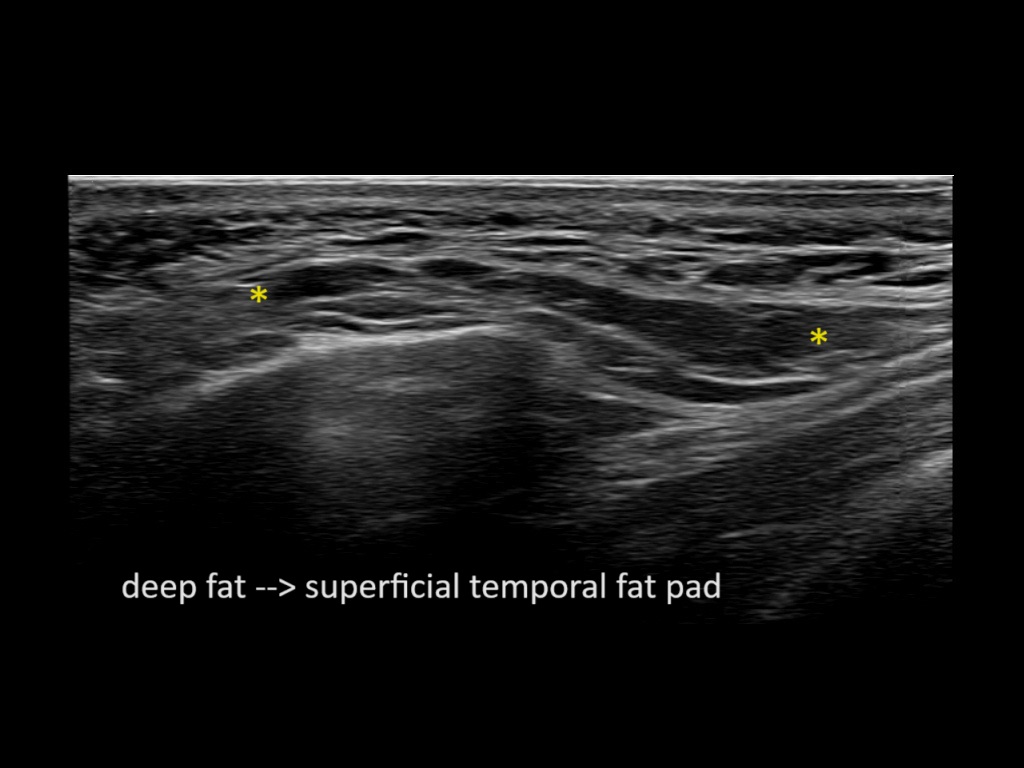

Study the first image to recognize the different layers. If you are sure about the layers, swipe to the second image to view the answer (if applicable).